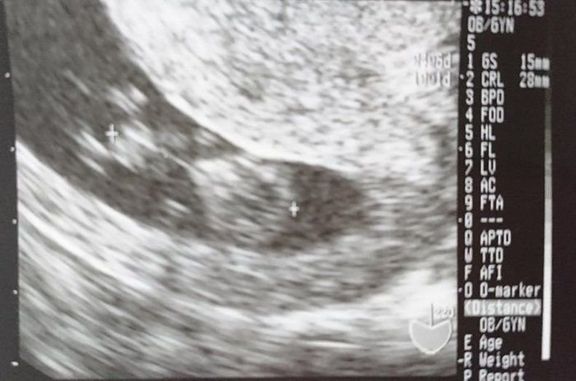

命の始まりは神秘的!2D・3D・4Dのエコー写真で見る「私と赤ちゃんの実録260日」 -

"おなかの中はどうなっていくの? エコー写真で振り返る、高齢ママのはじめての妊娠生活" -